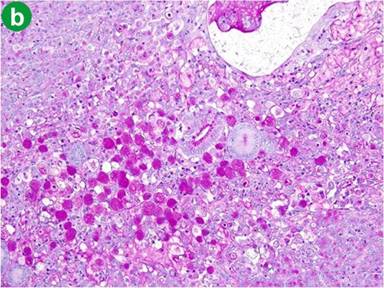

Macroscopically, the tumor measured 1.5x1.5x2 cm and the tumor surface was exposed at the papilla, showing that its surface was nodular, but there was no ulceration. Histologically, signet-ring cell carcinoma was predominant, but partially well- to poorly-differentiated tubular adenocarcinoma also existed in the lesion (Figure 3a). Signet-ring cell carcinoma arose from the ampulla of Vater, slightly involving the muscularis propria of the duodenum and infiltrating the pancreatic parenchyma. The cytoplasm of the signet-ring cell carcinoma was positive for periodic acid Schiff staining (Figure 3b). Lymphatic and vascular involvement was seen in parts, but resected lymph nodes were free from metastasis. Immunohistochemical staining was performed and both the signet-ring cells and the adenocarcinoma cells were positive for human gastric mucin (45M1) (Figure 4). Both types of tumor cells were positive for CK7, MUC1 and MUC6, but negative for CK20, MUC2 and CD10 (Figure 5). The signet-ring cell carcinoma was partially positive for CDX2 (Figure 6). The carcinoma of the ampulla of Vater was diagnosed as T3N0M0 stage IIA according to the International Union Against Cancer TNM classification. The patient did not receive chemotherapy. Six months after surgery, the patient developed pneumonia. Subsequently, the pneumonia worsened and the diabetes mellitus also deteriorated. The patient finally died from multiple organ failure due to sepsis. However, no recurrence of the signet-ring cell carcinoma was detected on repeated imaging studies.

Figure 3. Histopathological findings of the carcinoma. a. Signet-ring cell carcinoma co-existing with tubular adenocarcinoma (H&E x50). b. The signet-ring cell carcinoma was positive for periodic acid Schiff staining (H&E x50). |